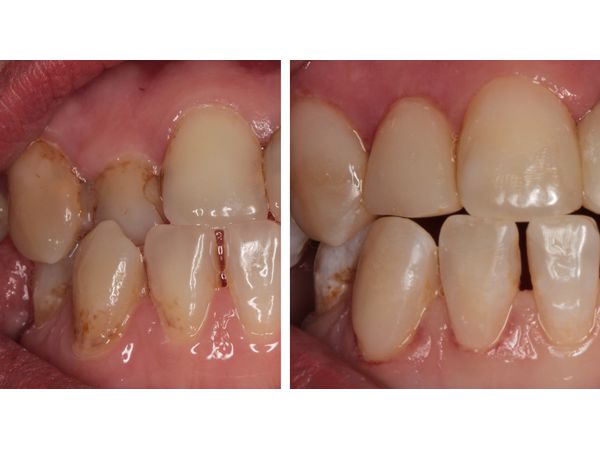

Улучшение внешнего вида пациентка отметила уже после первого визита, когда были восстановлены верхние зубы.

После проведённого лечения был достигнут предполагаемый эстетический результат.

Данный клинический случай подтверждает широкие возможности прямой реставрации в эстетической стоматологии. Кроме того, при определённых обстоятельствах (неприятие пациентом ортопедических конструкций, финансовые проблемы) метод прямой реставрации помогает скорректировать незначительные нарушения положения зуба в дуге и тем самым улучшить качество жизни пациента. Но следует отметить, что данная методика призвана помочь исключительно в эстетических целях и на зубах, не несущих существенной нагрузки